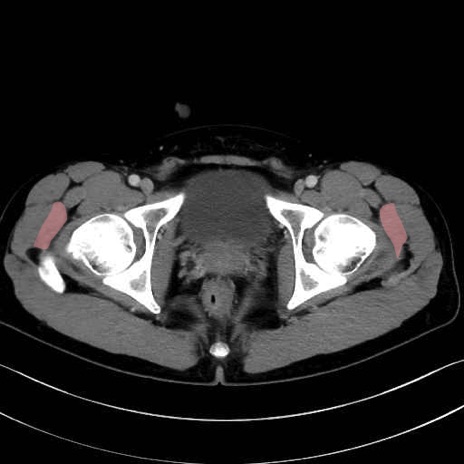

小殿筋 (Gluteus minimus)